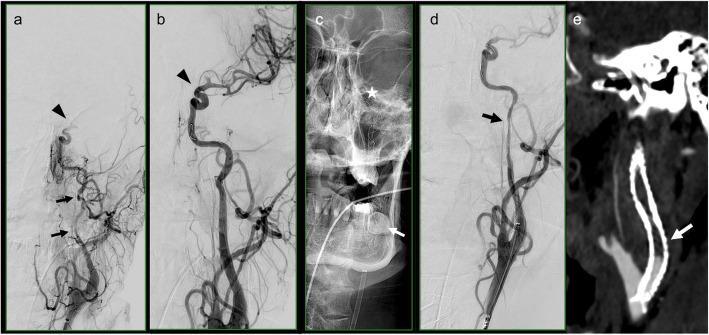

Endovascular therapy (EVT) for large intracranial vessel occlusion or symptomatic hypoperfusion due to cervical artery dissection (CeAD) became the standard therapy in recent years. Stenting is frequently required to secure the dissection with subsequent need for GP IIb/IIIa inhibitors. However, a potential concern of antithrombotic therapy in acute stroke is the increased risk of intracerebral hemorrhage. The aim of the study was to assess the impact of the administration of a GP IIb/IIIa inhibitor imaging during endovascular treatment for acute ischemic stroke caused by CeAD on 90-day clinical outcome and intracranial hemorrhage.

This single-center retrospective cohort study enrolled CeAD patients with internal carotid artery (ICA) dissections treated with EVT from January 2015 to August 2022. We analysed the impact of different variables including postinterventional hemorrhage, revascularization success and the use of GP IIb/IIIa Inhibitors (eptifibatide) on 90-day favorable clinical outcome (mRS 0-2). NIHSS Scores were evaluated at different time points in relation to the 90-day clinical outcomes.

Forty-nine patients were included in the study. Thrombectomy was performed in all patients. In 33 patients, stenting was performed in addition to thrombectomy. 20 patients (40.8%) received eptifibatide periinterventionally. 31 out of 49 patients (63.3%) had a favorable 90-day clinical outcome (mRS 0-2). Five patients showed radiologically significant hemorrhage. The rate of successful reperfusion (TICI 2b-3) in the favorable 90-day outcome group was significantly higher than in the unfavorable 90-day outcome group.